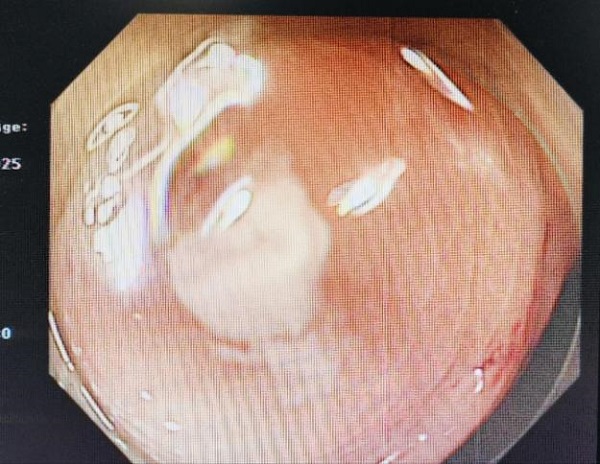

术中,张亚飞主任团队密切配合、熟练操作,通过肠镜(母镜)头端安置透明帽,循腔进镜至阑尾窝,可见阑尾内口黏膜水肿明显,有少量白色脓性分泌物,以一次性使用成像导管(子镜)进入阑尾腔内,可见阑尾粪石及较多脓性分泌物,反复冲洗吸引予以清除,后再次进镜至阑尾盲端,可见阑尾腔壁充血水肿,散在点状糜烂,未见残留粪石,逐步退出内镜,完成治疗。术后,张奶奶腹痛明显减轻,且无其他不适。整个微创手术在二十分钟内顺利完成,没有切口和出血,既保留了阑尾,又成功取出了阑尾粪石。